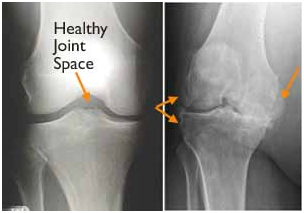

The most common condition that results in the need for knee replacement surgery is osteoarthritis.

Osteoarthritis is characterized by the breakdown of joint cartilage. Damage to the cartilage and bones limits movement and may cause pain. People with severe degenerative joint disease may be unable to do normal activities that involve bending at the knee, such as walking or climbing stairs, because they are painful. The knee may swell or “give-way” because the joint is not stable.

(Left) In this x-ray of a normal knee, the space between the bones indicates healthy cartilage (arrow). (Right) This x-ray of an arthritic knee shows severe loss of joint space and bone spurs (arrows).